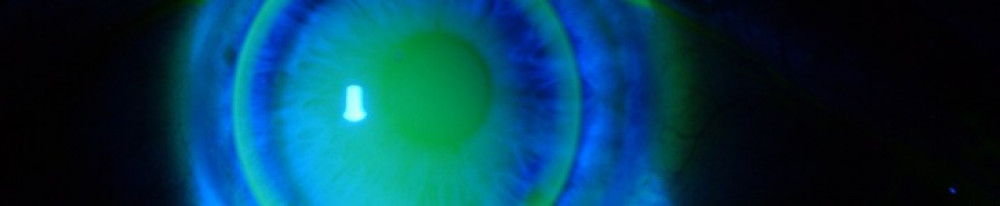

We provide a contact lens assessment, fitting, prescribing and aftercare service for patients of Leeds Teaching Hospitals NHS Trust requiring clinically necessary contact lenses. We provide a specialist contact lens service including cosmetic, paediatric, therapeutic and keratoconic contact lenses. We provide this service for adults at the main eye clinic, Level 04, Gledhow wing at St. James’s University Hospital and for our paediatric patients in the Multi Speciality Outpatients (MSO) at St. James’s University Hospital.